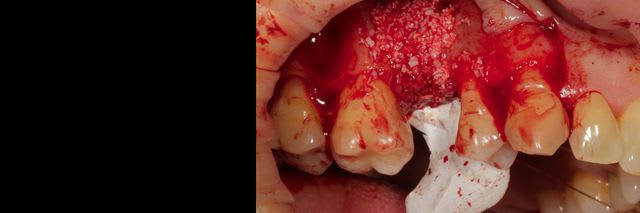

Bon ben voilà j'ai réalisé une ROG avec une membrane PTFE armé titane.

bien sûr les photos sont dans le désordre encore une fois ;)